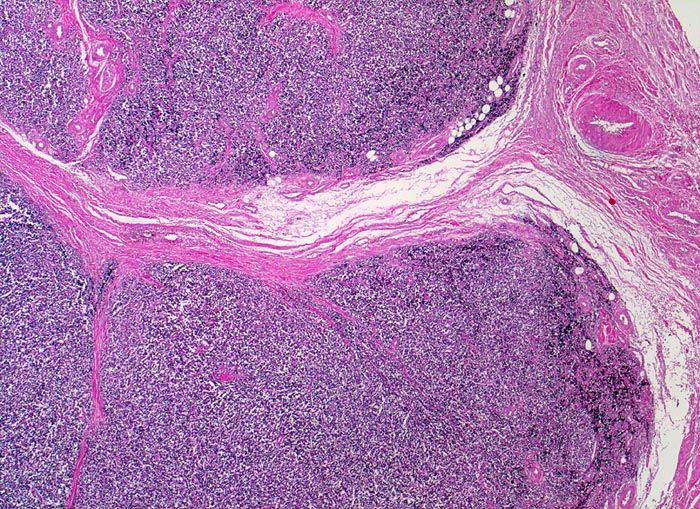

Ewing-Sarkom

Weichteile Bein

Auffallend monotoner dichter Tumorzellrasen mit lobulärer Architektur (d.h. durch Bindegewebssepten abgegrenzte Knoten).

Femuramputat mit festem grauweissem intraossärem feucht-glänzendem Tumorgewebe. Die extraossäre Weichteilkomponente ist weicher und brüchiger. Der Gewebsschnitt stammt aus der extraossären Weichteilkomponente.

Die Ewing Sarkome gehören zur morphologischen Gruppe der "small blue round cell" Tumoren. Zu dieser heterogenen Gruppe aus kleinen runden Zellen bestehenden Tumoren gehören neben den Ewing Sarkomen die verwandten primitiven neuroektodermalen Tumoren (PNET), Rhabdomyosarkome, Neuroblastome, kleinzellige Lymphome, wenig differenzierte und kleinzellige Karzinome, Merkelzellkarzinome, maligne Mesotheliome, kleinzellige Melanome und desmoplastische klein- und rundzellige Tumoren. Weil diese unterschiedlichen Tumoren morphologisch sehr ähnlich sein können, braucht es exakte klinische Angaben und Hilfsuntersuchungen (Spezialfärbungen, Immunhistochemie, molekularbiologischer Nachweis spezifischer zytogenetischer Veränderungen) für eine korrekte Diagnosestellung.

25